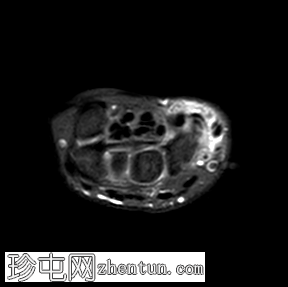

轴位

T1加权像

轴位PD脂肪抑制像

桡掌侧舟状骨-大多角骨韧带低信号,符合钙化灶,周围伴软组织水肿和舟月关节积液。